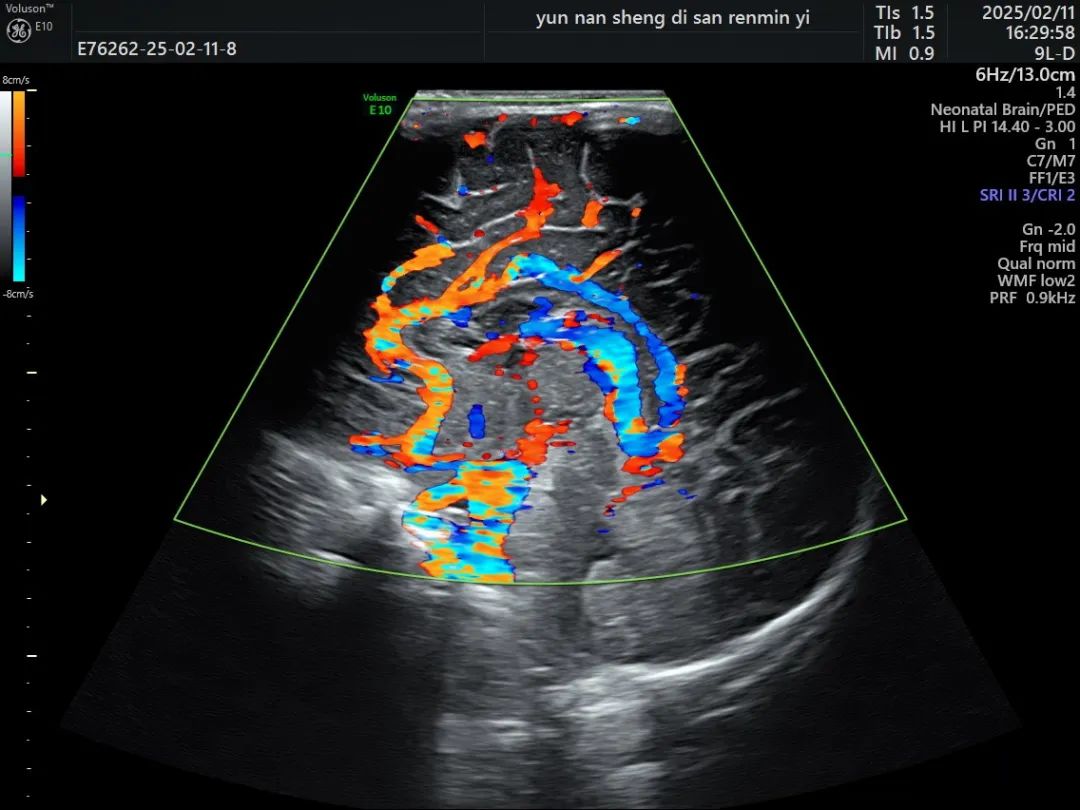

小儿颅脑超声检查是通过超声仪器,利用尚未闭合的囟门(如前囟、乳突囟、后囟等)作为声窗,对颅内结构进行扫描和观察。这种方法可以清晰地显示大脑、小脑、脑干等重要结构,以及颅内血管的情况,是一项可以与头颅核磁共振相媲美的检查方式。

超声检查能够帮助医生早期发现颅内出血、脑积水、脑损伤、感染等疾病,为临床治疗提供重要依据。

(颅脑超声血流图)